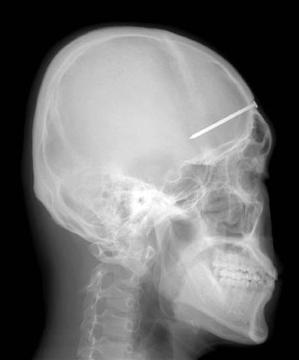

7. Kecelakaan Nailgun

X-ray Patrick Lawler, 23 menunjukkan empat inci paku tertanam di kepalanya, diambil bulan Januari 2005. Kecelakaan itu terjadi 6 hari lalu ketika Lawler mengalami kecelakaan konstruksi di mana nailgun menjadi bumerang dan satu paku menembus mulutnya. Dia tidak melihat paku di mulutnya hanya sampai ia merasakan sakit gigi yang sangat menyakitkan disertai dengan visi yang kabur.

Setelah kunjungan ke dokter gigi dia menyadari apa yang ada di dalam kepalanya selama hampir satu minggu. Itu dihapus setelah 4 jam operasi meninggalkan dia dengan kurang dari US $ 100,000,- tagihan rumah sakit. Oh tidak.